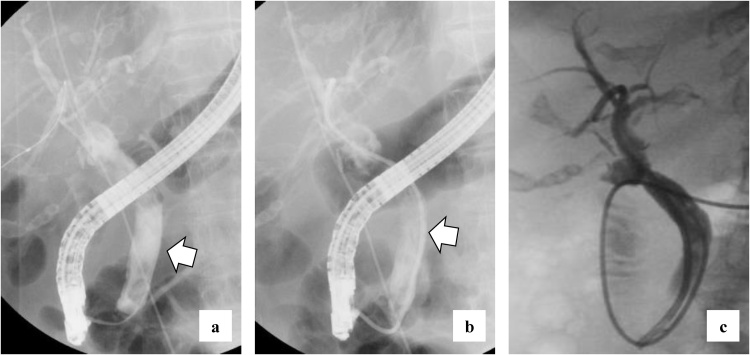

She complained of back pain and right hypogastric pain on postoperative day (POD) 12. Blood examination revealed anemia and elevated levels of serum bilirubin and hepatobiliary enzymes. The total bilirubin (T-bil) level was 2.73 mg/dL (normal range: 0.2–1.2 mg/dL), direct-bilirubin (D-bil) level was 2.36 mg/dL (normal range: 0–0.4 mg/dL), aspartate aminotransferase (AST) level was 243 U/L (normal range: 10–40 U/), alanine aminotransferase (ALT) level was 82 U/L (normal range: 5–40 U/L), alkaline phosphatase (ALP) level was 2018 U/L (normal range: 100–340 U/L), and hemoglobin (Hb) level was 6.5 g/dL (normal range: 12–15 g/dL). Computed tomography (CT) revealed a high absorption area in the common bile duct (CBD), and hemobilia was suspected (Fig. 1a). Contrast-enhanced CT revealed no active bleeding into the abdominal cavity, but a pseudoaneurysm was observed in the cystic artery (Fig. 1b). Endoscopic retrograde cholangiopancreatography (ERCP) revealed contrast deficiency in the CBD, although there was no leakage of contrast outside the CBD (Fig. 2a). An ENBD tube was inserted on POD 12 (Fig. 2b) and an ERBD stent was placed in the CBD on POD 13. The fluid drained from the ENBD tube was a mixture of blood, bile, and pus, and was suggestive of a superimposed bacterial infection. A diagnosis of hemobilia was made as the fluid drained from the ENBD was blood. The patient also presented with melena. Therefore, conservative treatments, such as blood transfusion and administration of antibiotics, were commenced. Due to gradual deterioration of renal function (eGFR reduced to 7 mL/min/1.73 m2) and reduction in urine output during the treatment, hemodialysis was temporarily introduced on POD 15. After controlling hemobilia and biliary infection, renal function improved (eGFR increased to 23 mL/min/1.73 m2) and hemodialysis was discontinued on POD 30. Blood-based investigations revealed that the levels of hepatobiliary enzymes were improving gradually, while contrast examination using the ENBD tube showed no leakage of the contrast medium outside the CBD on POD 27 (Fig. 2c). The ENBD tube was removed on POD 27, the ERBD stent was removed on POD 54, and she was discharged on POD 66.